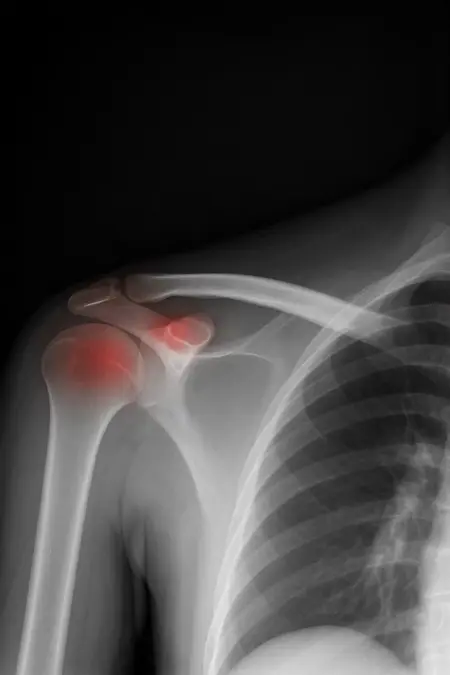

アートや写真の編集用に設計されたFlux Kontextのようなモデルを、医療画像、たとえば「単純な」骨折の赤色マーキングに使用できるか?

即答:面白い結果を出すが、過剰に反応し、医療ツールとしては信頼性に欠ける。これはアイデアを試すためのプロトタイプに過ぎない。

テスト結果:

- 偽陽性 ≈ 24%

- 骨折検出 ≈ 20%

感度モード(検出を優先、ノイズ多め)

- Euler、15ステップ、Karras

- Denoise:1.0

結果:

- 偽陽性 ≈ 80%

- 骨折検出 ≈ 86%